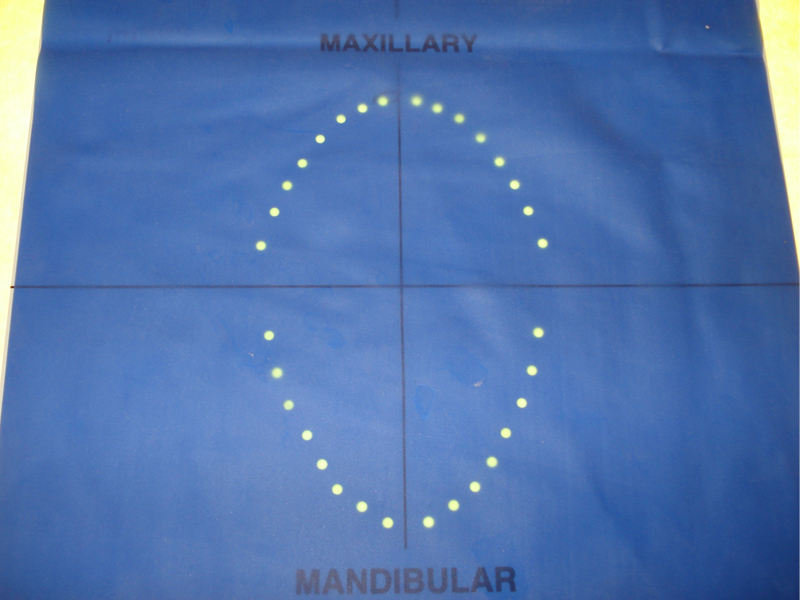

Jeder Zahn besteht aus einem sichtbaren Teil, der Zahnkrone sowie einem von Zahnfleisch und Knochen umgebenden unsichtbaren Teil, der Zahnwurzel. Es gibt eins, zwei oder dreiwurzelige Zähne somit ist die Wurzelanzahl sowie die Wurzelform je nach Zahn unterschiedlich.